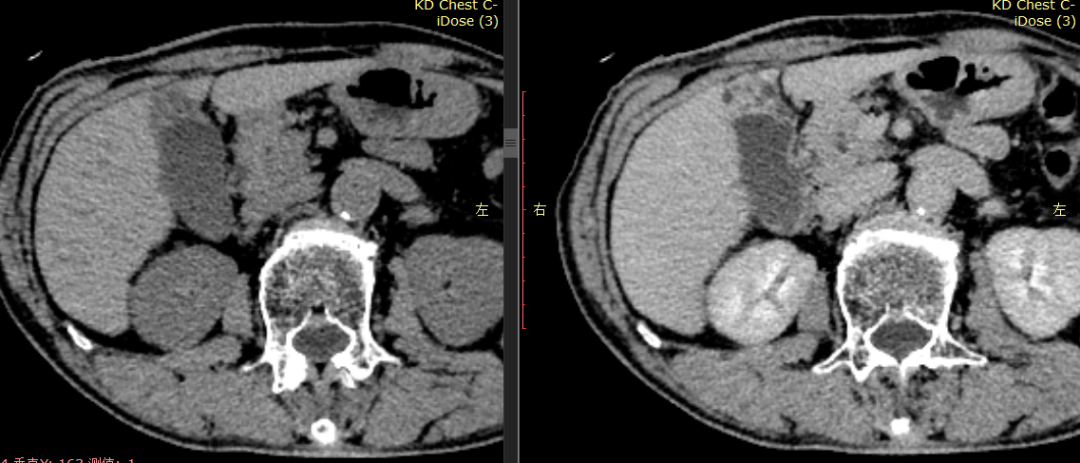

CASE 2